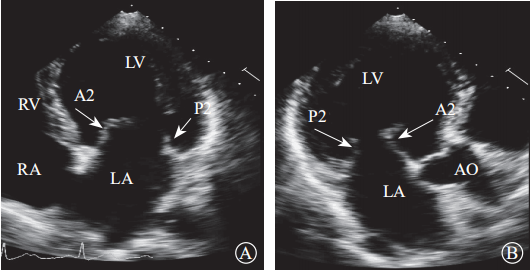

注:LA,左心房;LV,左心室;RA,右心房;RV,右心室

图 6 经胸二维超声心动图显示二尖瓣瓣叶各扇叶 A. 心尖四腔心切面,显示二尖瓣前叶 A2 处、二尖瓣后叶 P2 处;B.心尖长轴切面,显示二尖瓣前叶 A2 处、二尖瓣后叶 P2 处

注:LA,左心房;LV,左心室

图 7 经胸二维超声心动图显示二尖瓣瓣叶各扇叶 A. 心尖二腔心切面,显示二尖瓣前叶 A1处、二尖瓣后叶 P3 处;B.二尖瓣交界处长轴切面,显示二尖瓣后叶 P1、前叶 A2、后叶 P3